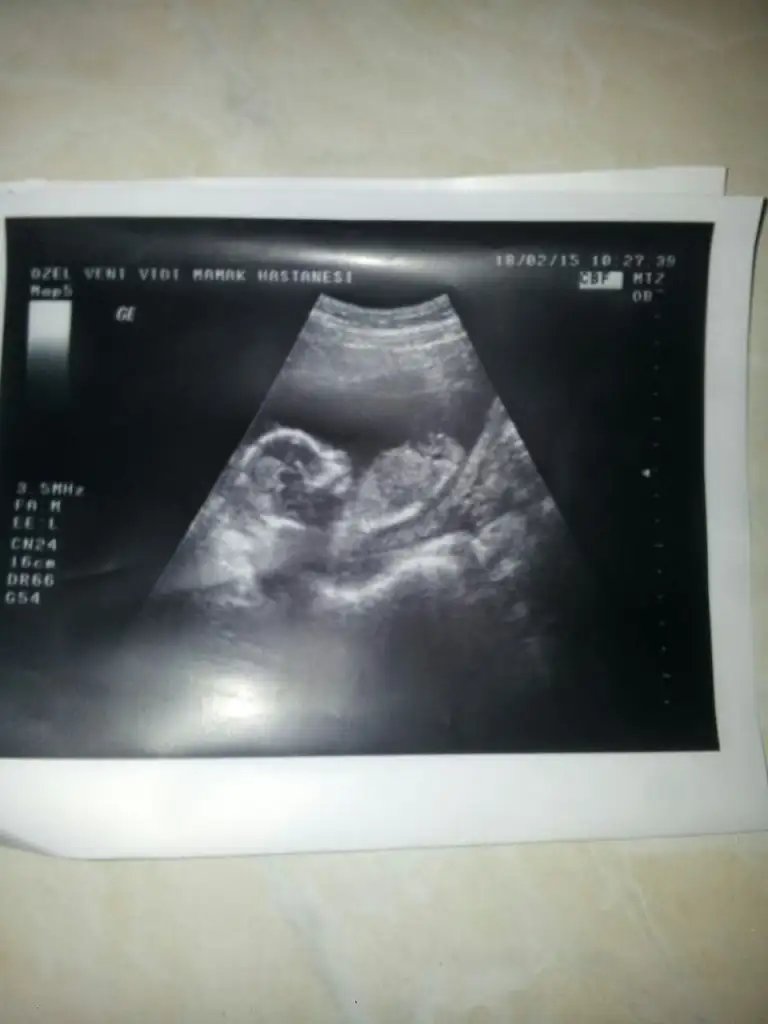

dr soylemeden siz gorun genital nub teorisi ( bebegin cinsiyeti)

Doktor göremiyorum ama erkek olabilir dedi. Çok kafam karıştı ya:)

Yok yok ne arar dönmedi ki sıpa:) doktor şurada pipiye benzer bişey görüyorum ama emin değilim dedi. Haftaya tekrar gidecem ama görememekten korkuyorum. Gidip şak diye görmek istiyorum ya